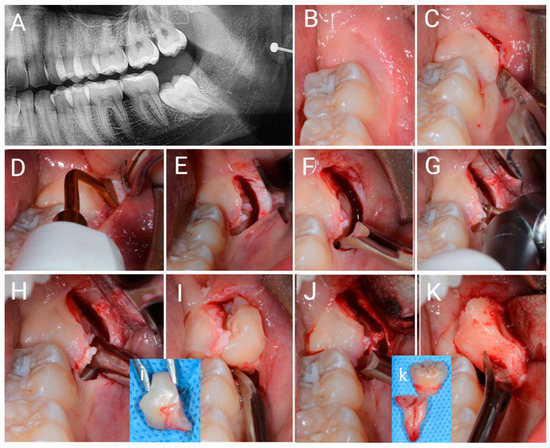

2.4. Surgical Design

2.4.2. SIA Surgical Design

2.5. Post-Surgical Treatment and Procedure